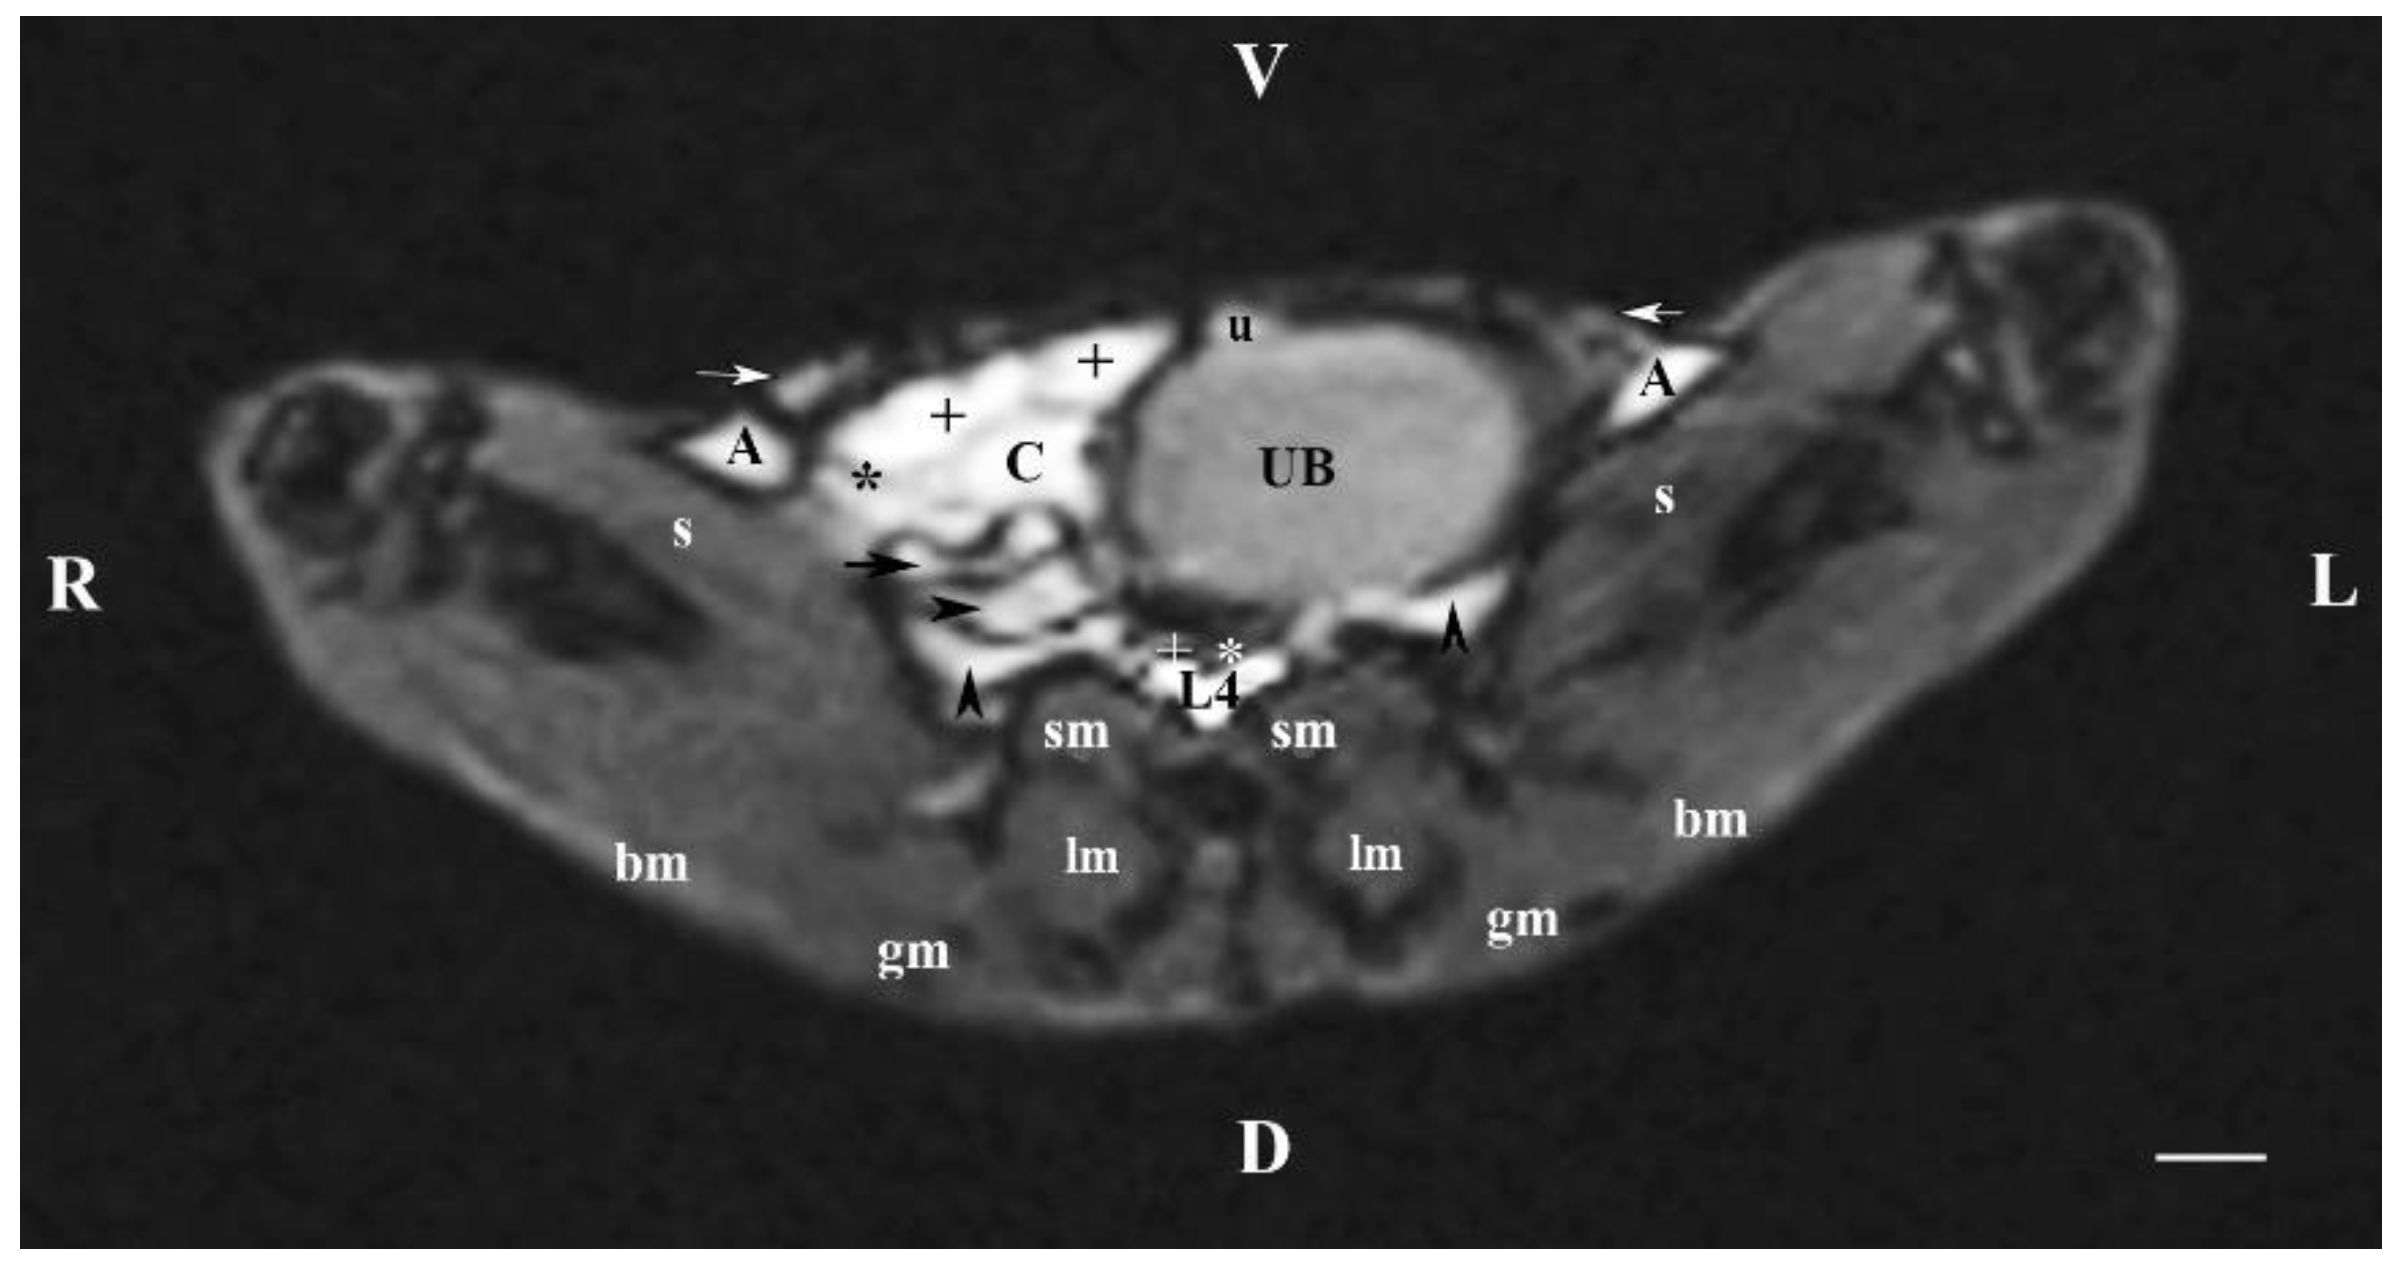

In the transverse plane through L4 (T1-weighted sequence), the filled cranial part of the urinary bladder demonstrated flexion to the left with localization of the organ in the left caudal abdomen with exception of the bladder neck. Therefore, the other abdominal organs in this part of the abdomen were displaced to its right part, where the ileum, the ascending colon, the caecum, jejunal loops and the attached mesentery were visualized. Dorsally, only the hyper intense images of duodenal parts were situated, appearing as heterogeneous hyper intense findings in comparison to the urinary bladder image. Cranially, a part of the urachus was seen, again hyper intense vs the urinary bladder. The transverse hypo intense images of the caudal vena cava and the abdominal aorta were visualized ventral to the body of L4 and dorsomedial to the urinary bladder. The urinary bladder image was dorsoventrally flattened and oval, with heterogeneous and relatively hypo intense lumen in relation to the MR features of the other abdominal organs. The T1-weighted sequence of the urinary bladder defined distinctly its borders from the adjacent soft tissues. The lumen of the studied organ was relatively hyper intense vs its hypo intense wall. The images of the dorsolaterally positioned muscles (sartorius, spinal, longissimus, biceps and gluteus muscles) were relatively hypo intense than that of the bladder. On this section, ureter findings were not presented (Figure 4).

The results from transverse MRI of the urinary bladder through L4 (T2-weighted sequence) confirmed its localization to the left. The flexion of the bladder in this direction is caused by the large caecum situated in the caudal right part of the abdominal cavity. The image of the urinary bladder lumen was relatively hyper intense unlike that of its wall (hypo intense), and at the same time, it is hypo intense in relation to adjacent abdominal organs due to the option of T1-weighted sequence.

Figure 4. MRI imaging anatomy of organs from the middle abdominal region (transverse section at the L4 level); R-right; L-left; D-dorsal; V-ventral; (T1-weighted sequence). (UB) urinary bladder; (+) jejunum; (*) mesenterium; (C) caecum; (black horizontal arrow) ileum; (black horizontal arrowhead) ascending colon; (black vertical arrowhead) duodenum; (A) adipose tissue; (s) sartorius muscle; (sm) psoas muscles; (lm) longissimus muscle; (gm) gluteus muscle; (bm) biceps femoral muscle; (white horizontal arrows) abdominal wall; (white cross) caudal vena cava; (white star) abdominal aorta; (u) urachus and median ligament of urinary bladder. Line=10mm.